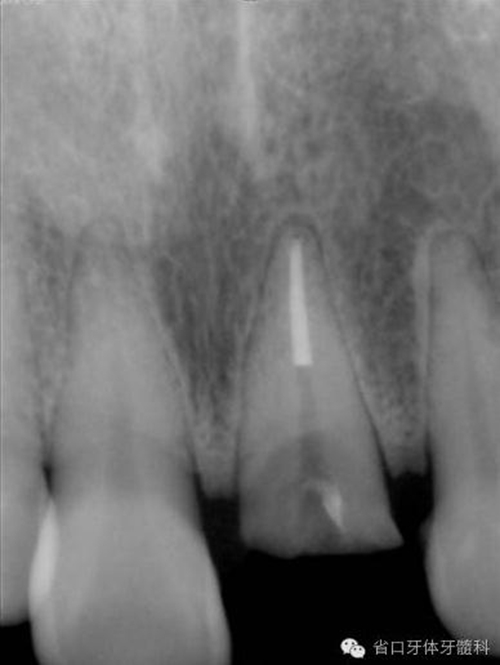

圖8. 21/行根管治療術(shù),保留根尖約5mm的根充物,根中上段預(yù)留空間以預(yù)備纖維樁道。

圖17. 術(shù)后X線片